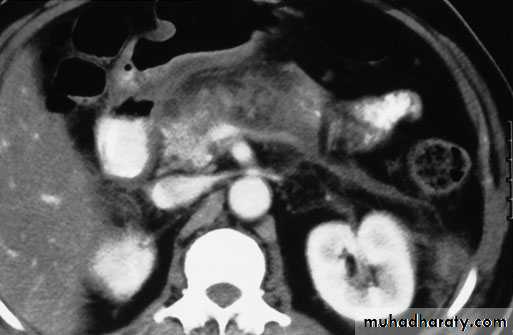

Imaging studies:

plain X ray of the abdomen

CXR in erect position.

U/S and/or CT Scan.